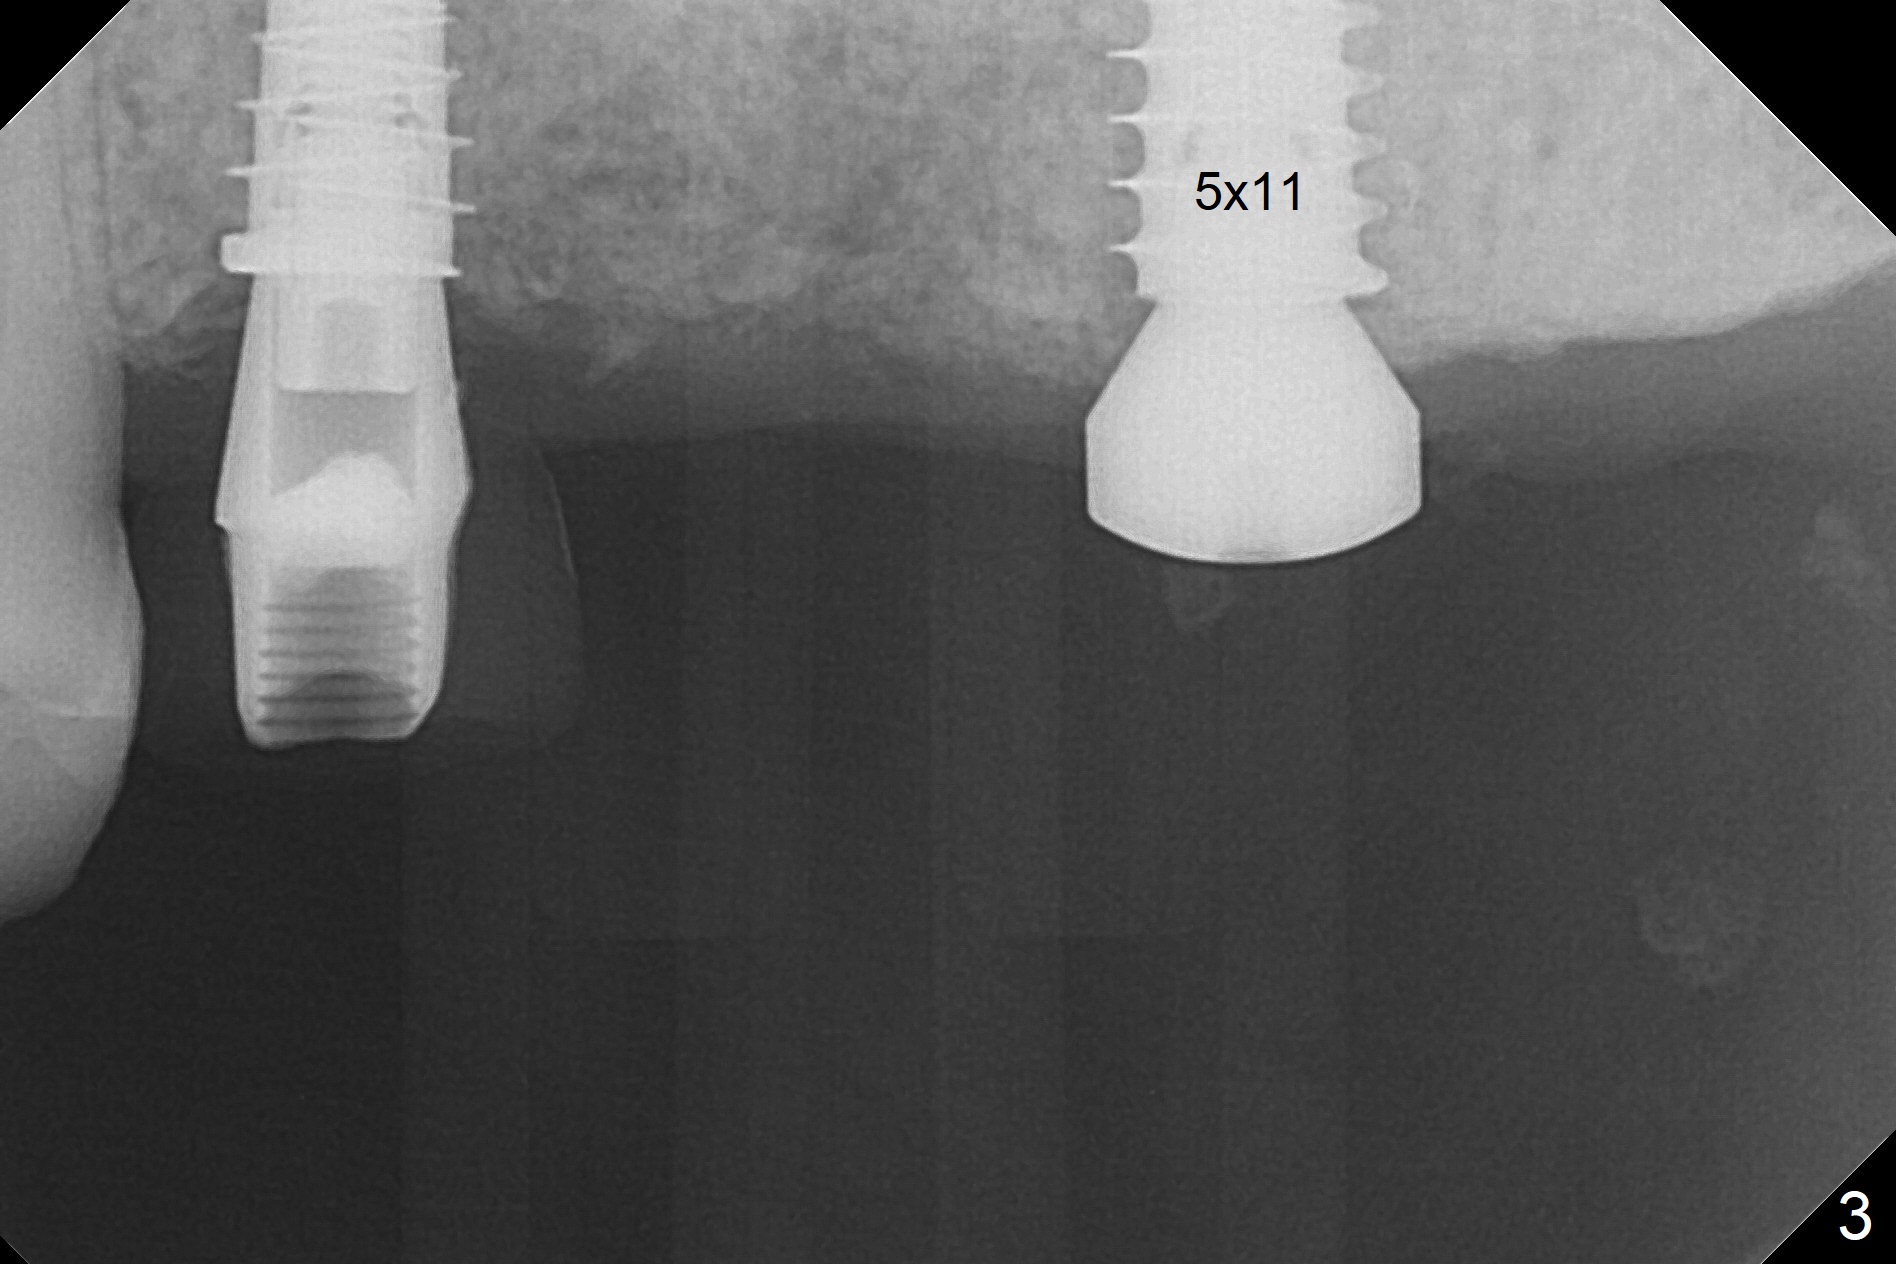

A fistula is found apical to #13 immediate implant 9 months postop (Fig.1). It is curetted without bony defect. Osteotomy at #15 is accomplished with traditional tapered osteotomes from 2 to 5 mm for 11 mm deep. Although the patient is a little uncomfortable with tapping (as compared to Magic Expanders), a 4.5x11 mm dummy implant is placed 2 mm subgingival with primary stability (Fig.2). Finally a 5x11 mm IBS implant (2 mm longer than the previous one) is placed with insertion torque > 50 Ncm; a 6x2 mm healing abutment is placed (Fig.3,4). The advantages of the flapless surgery (because of the wide ridge) include no allograft or suture. The fistula apical to #13 implant disappears 3 days postop (Fig.5), while the gingiva attaches to the healing abutment at #15 (Fig.6).